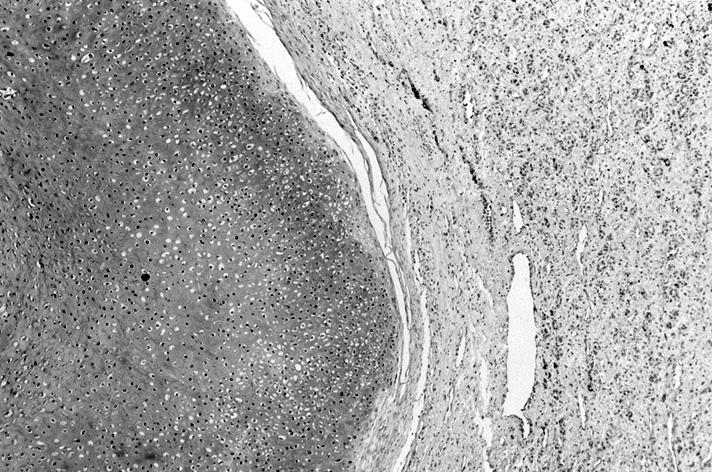

Microscopic (histologic) images

Contributed by Shipra Agarwal, M.D., Andrey Bychkov, M.D., Ph.D., Mark R. Wick, M.D., Asmaa Gaber Abdou, M.D. and AFIP

Atypical adenomas:

Not invasion:

- No capsular or vascular invasion after thorough sampling (at least 10 blocks)

- Encapsulated; thin or moderately thick capsule